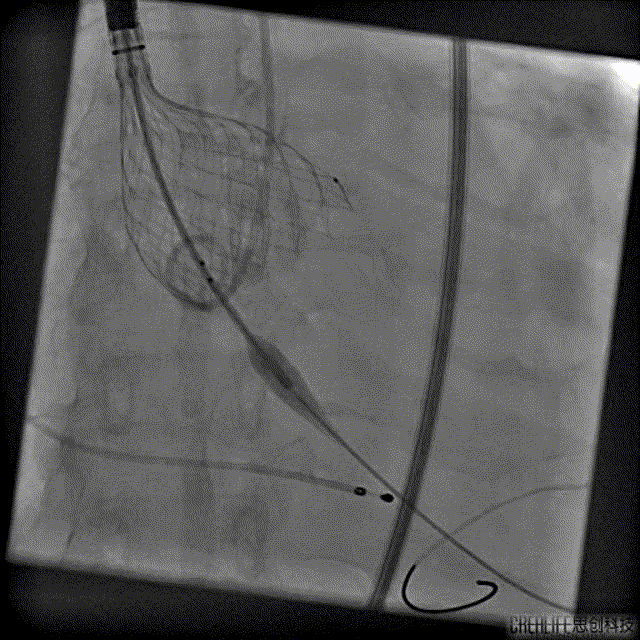

术中:

根部造影

Numed25预扩

Venus32上跳

Venus32回收

VenusAplus32释放

ICE辅助下TAVR手术

造影大量反流

VenusA32瓣膜瓣中瓣

最后一枪造影